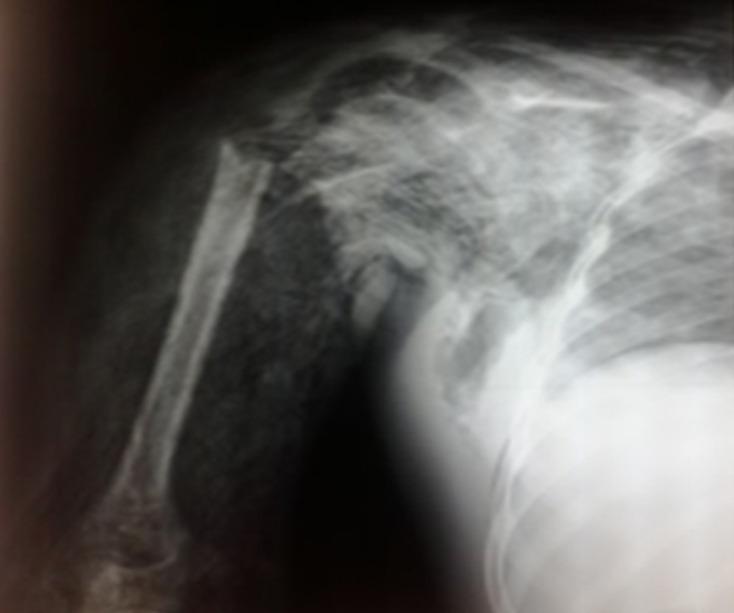

Scapulothoracic dissociation due to a trauma is exceptional. The purpose of this study was to share our experience with a case of scapulothoracic dissociation and to explain the advantages of our approach. We report the case of a 12-year-old right-handed schoolgirl admitted to hospital with a blunt trauma to the right thoracic limb complicated by infection after a week of traditional treatment (massage, bandaging with reed splints). Surgical neck fracture of the right humerus complicated by wet gangrene of the entire limb and severe anaemia was diagnosed. Blood transfusion, triple antibiotic therapy and scapulohumeral disarticulation were required. Progressive excision of necrotic tissue followed by scapulectomy (day 24) for scapular necrosis made it possible to sterilise the site and to perform a skin graft (day 43). The patient was discharged after 2 months. Physiotherapy was combined with psychological treatment and the patient had a simple post-operative course during the 7-month follow-up period. Failure of conventional treatment for limb fractures can be life-threatening and cause severe sequelae.